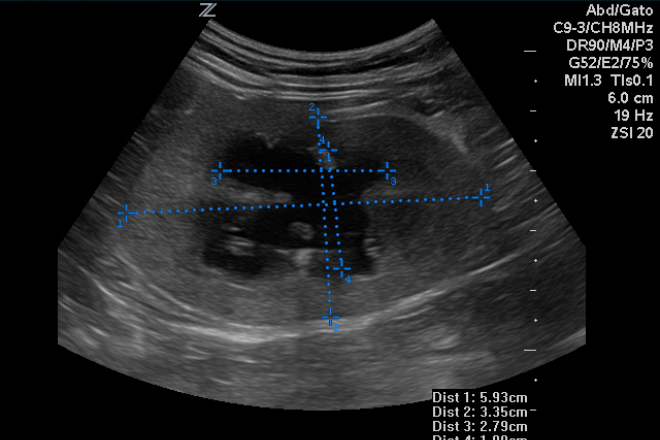

El cáncer de páncreas

El páncreas es un órgano glandular en el sistema digestivo y endocrino que es responsable de la producción de muchas hormonas; la insulina, la somatostatina (inhibición de la hormona del crecimiento de la hormona) y GlucaGen (importante para el metabolismo de hidratos de carbono). Como una glándula exocrina (segrega hormonas